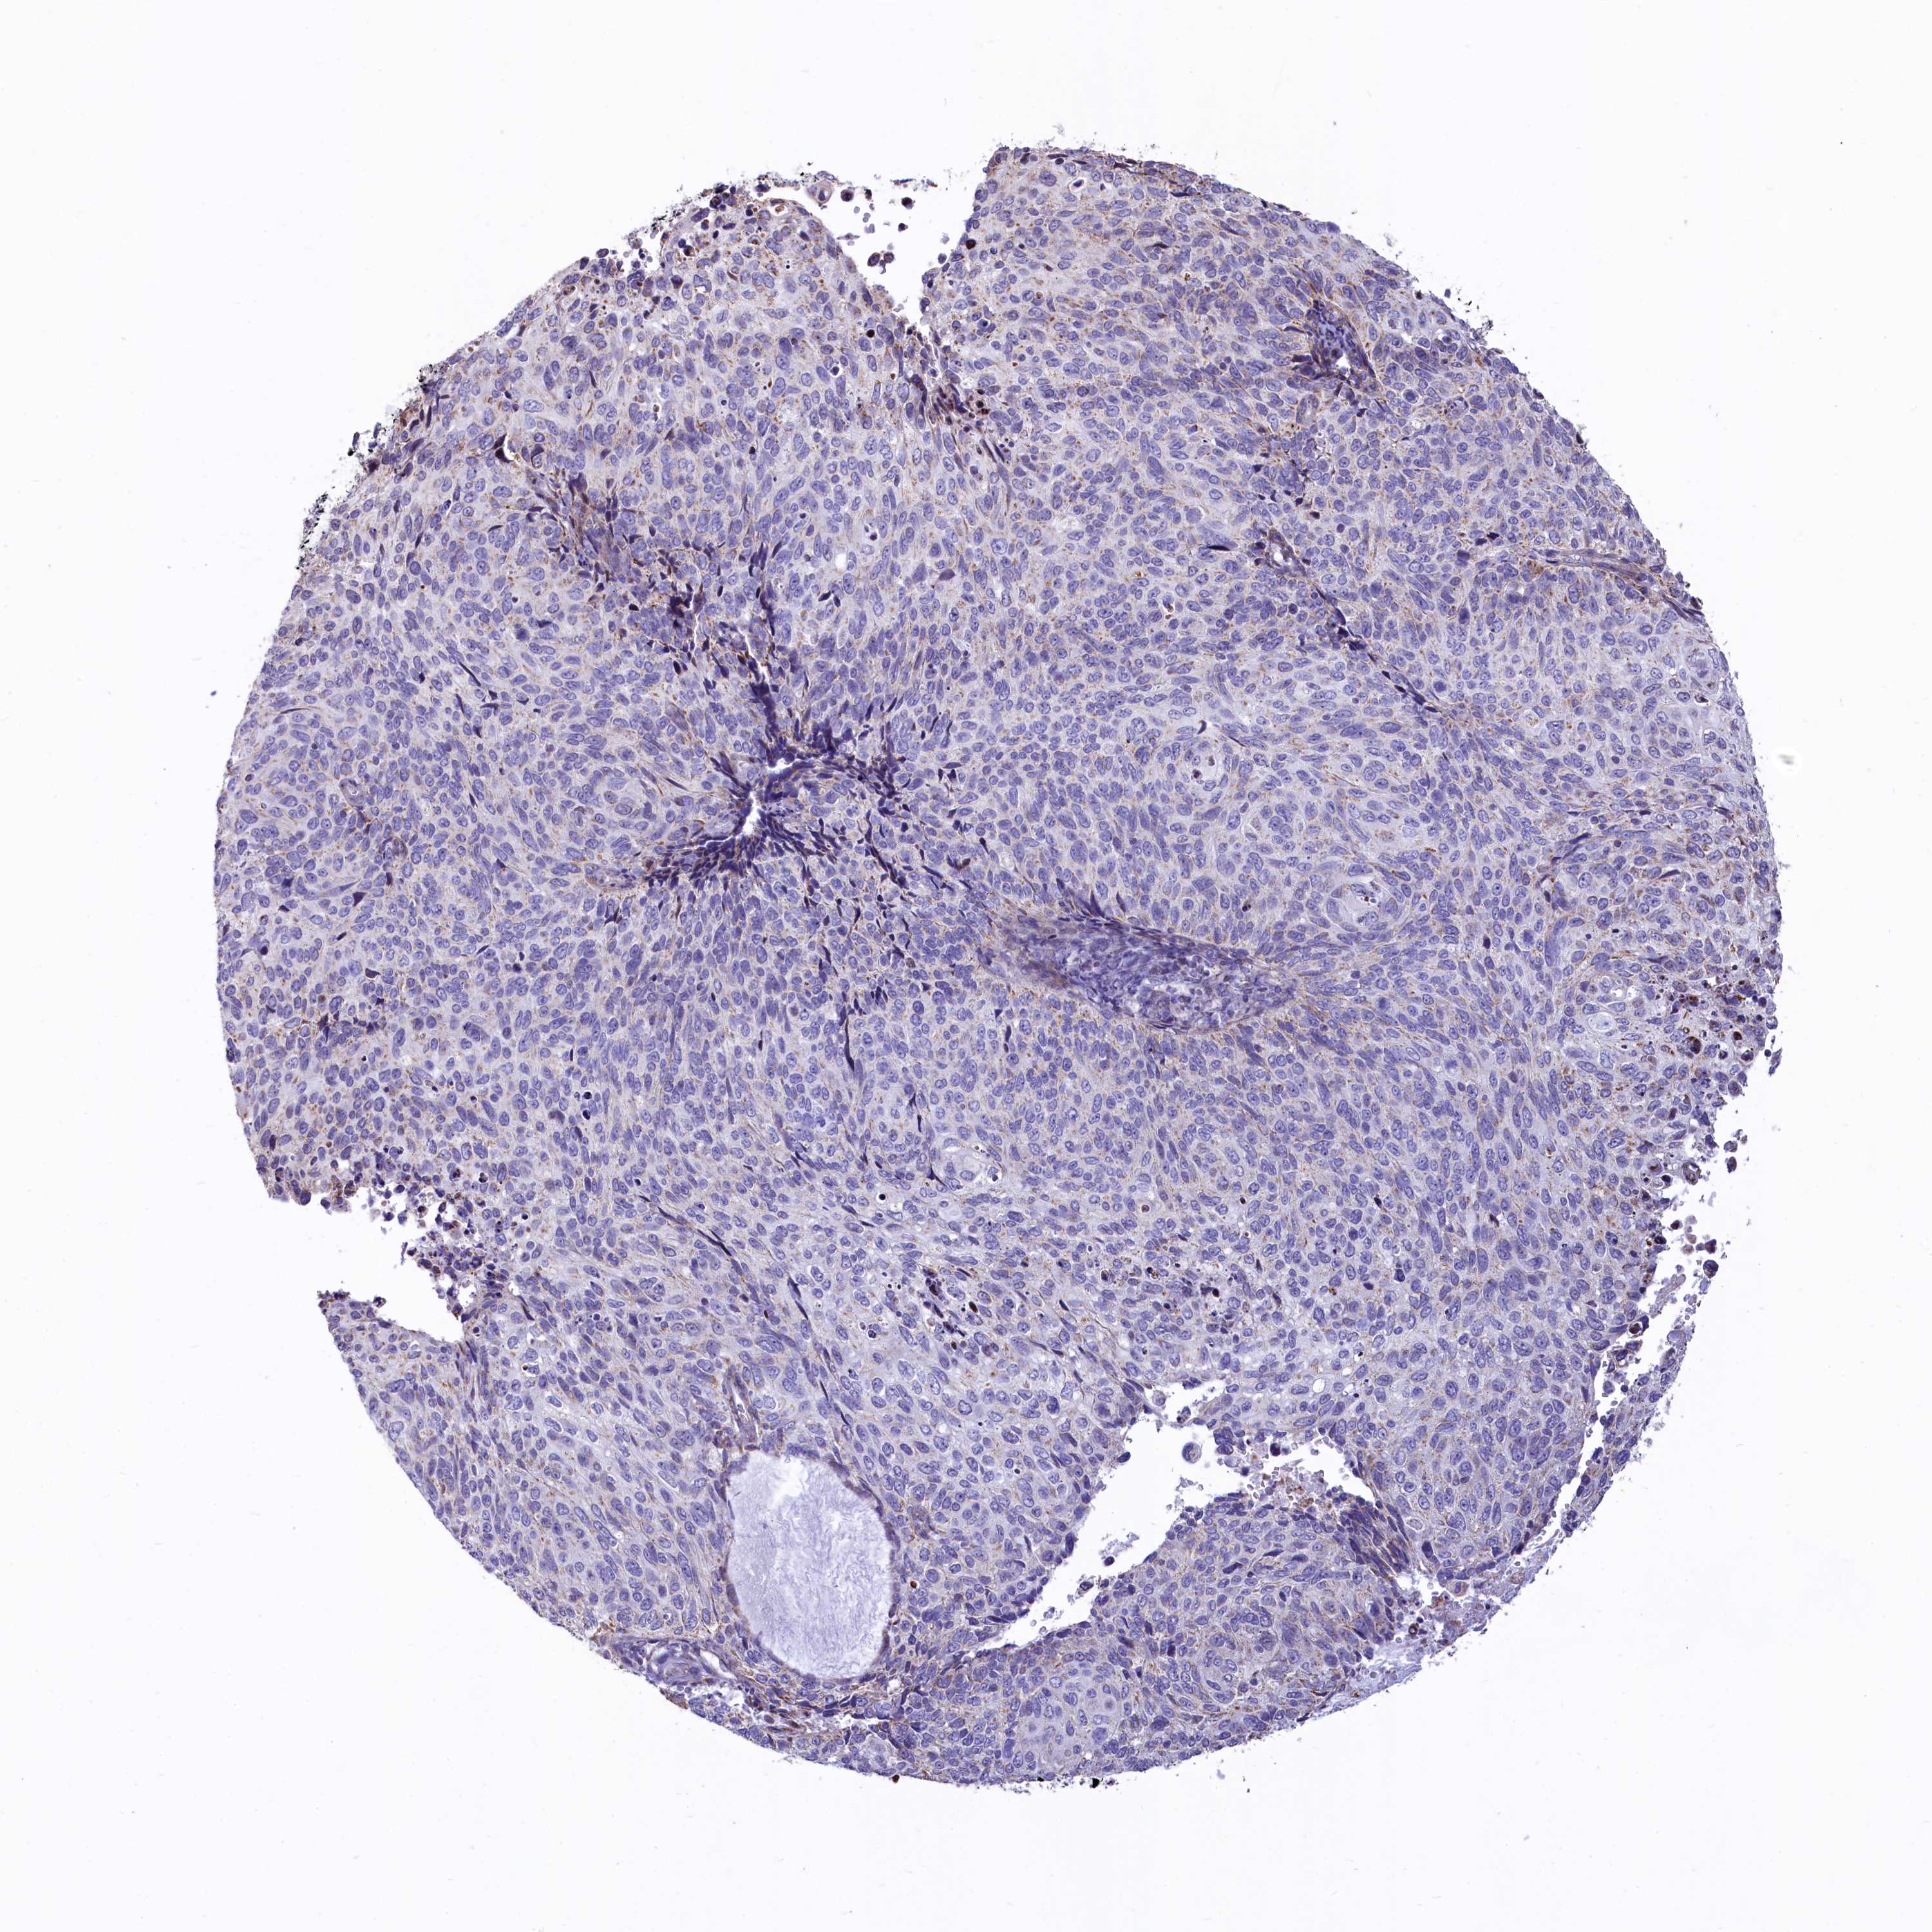

CERVICAL CANCER - Protein expressioni

A mouse-over function shows sample information and annotation data. Click on an image to view it in a full screen mode. Samples can be filtered based on level of antibody staining by selecting one or several of the following categories: high, medium, low and not detected. The assay and annotation is described here.

Note that samples used for immunohistochemistry by the Human Protein Atlas do not correspond to samples in the TCGA dataset.

Antibody stainingi

Antibody staining in the annotated cell types in the current human tissue is reported as not detected, low, medium, or high, based on conventional immunohistochemistry profiling in selected tissues. This score is based on the combination of the staining intensity and fraction of stained cells.

Each image is clickable and will lead to virtual microscopy that enables deeper exploration of all samples and also displays staining intensity scores, fraction scores and subcellular localization as well as patient and tissue information for each sample.

Antibody HPA040401

Antibody HPA043921

Staining

High

Medium

Low

Not detected

Intensity

Strong

Moderate

Weak

Negative

Quantity

>75%

75%-25%

<25%

None

Location

Nuclear

Cytoplasmic/membranous

Cytoplasmic/membranous,nuclear

Squamous cell carcinoma, NOS

Adenocarcinoma, NOS